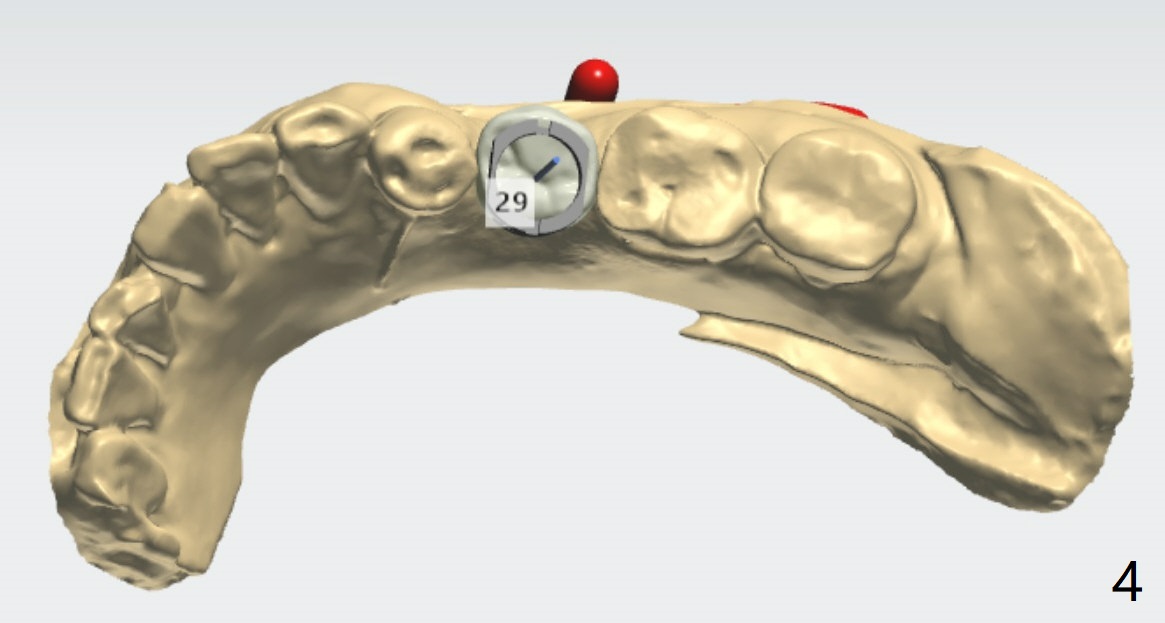

颊侧骨板缺失植骨后